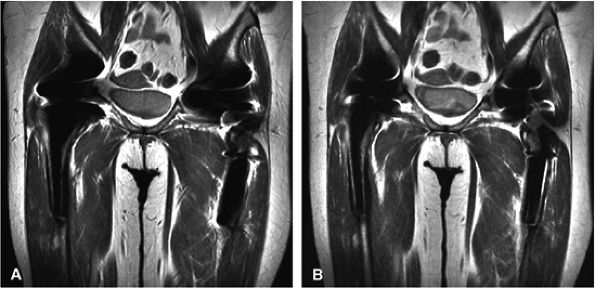

FIGURE 1.26 ● Hip examination, coronal fast spin-echo proton density-weighted image with FatSat (TR 3100, TE 41). (A) Images acquired with a four-channel cardiac array coil. (B) Images acquired with a body coil. The signal-to-noise improvement with the array coil is at least 100%.

|